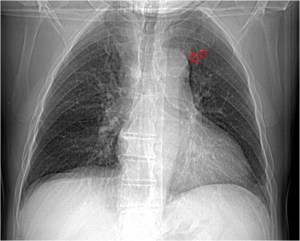

SIGNO DE LA JOROBA DE HAMPTON

Opacidad en cuña con base de contacto pleural, generalmente sin broncograma aéreo, que corresponde a infarto pulmonar. Aunque con frecuencia se localiza en el seno costofrénico lateral, puede encontrarse en otras localizaciones. La fotografía muestra una radiografía PA de tórax donde se observa una joroba de Hampton en el campo medio pulmonar derecho (flecha).